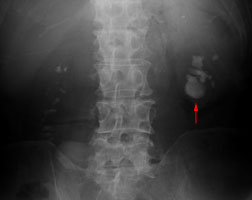

7.巨大腎臓結石(将来手術) |

|